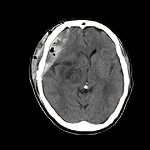

’12_126

'12年7月

50代

星状細胞腫

断層撮影

手術前1

手術後

No.’12_126 手術前1

No.’12_126 手術後